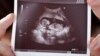

کوچه‌پس‌کوچه‌های بازار زیرزمینی «فایزر سقط‌جنین» در ایران

میفپریستون شرکت فایزر یکی از داروهای معتبر برای سقط‌جنین شناخته می‌شود

کنترل بارداری و یا سقط‌جنین در سال‌های اخیر جزو اقدامات ممنوع در ایران اعلام شده، مگر با مجوزهای قانونی، ولی زیرزمین‌ها همچنان فعال‌اند و سقط‌های پرخطر در آن انجام می‌شود.

علاوه بر این، قرص‌های سقط‌جنین هم در بازار در دسترس است؛ ازجمله داروهایی که به اسم فایزر آمریکایی فروخته می‌شود و فروشنده‌ها می‌گویند اثرگذاری‌شان تضمینی است.